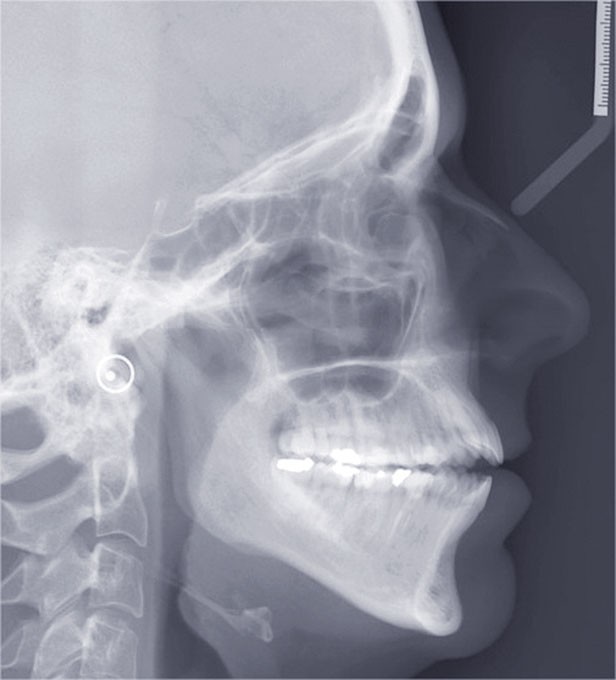

Il a été décidé de mettre en œuvre une thérapeutique avec brackets vestibulaires Damon afin d’optimiser l’expansion des arcades, la fermeture de la béance et la réduction du sourire gingival latéral qui perturbe l’esthétique du sourire de la patiente.

L’esthétique faciale de la patiente s’est nettement améliorée (fig. 7, 8, 9 et 10). On remarquera la réduction du sourire gingival…